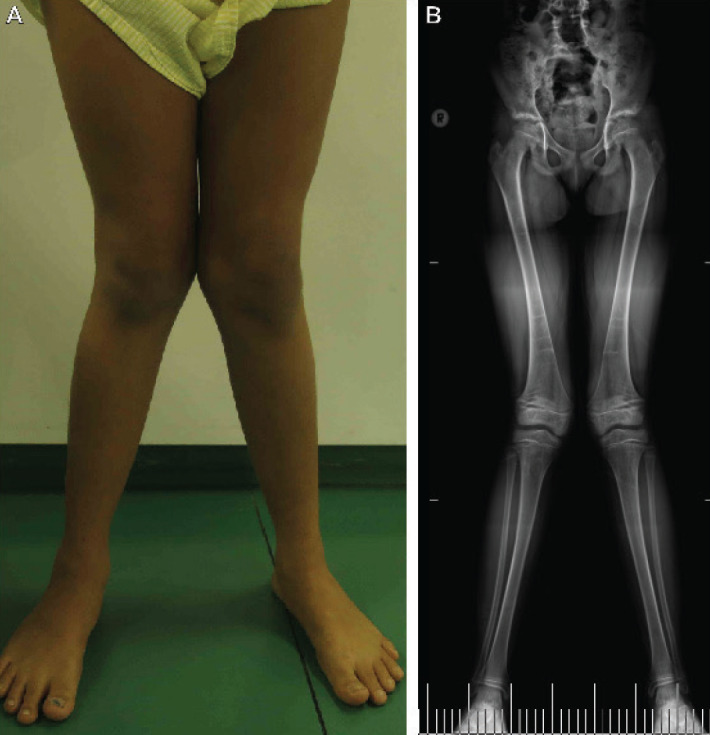

遗传性低磷血症佝偻病伴高钙尿症(HHRH)是一种罕见的由SLC34A3基因双等位基因变异引起的不依赖于成纤维细胞生长因子23的疾病。疾病的严重程度各不相同,患者发生肾脏并发症的风险增加。磷酸盐补充是标准的护理,活性维生素D类似物不建议,因为它们可能加重高钙尿症。我们报告一个巴西女孩与hrh谁提出膝盖疼痛和进行性膝外翻畸形,从8岁开始变得明显。肾钙质沉着症也在13岁时被确诊。针对佝偻病遗传形式的新一代靶向测序检测到SLC34A3的复合杂合致病变异,包括一种新的错义变异c.1217G>T (p.Gly406Val)。口服磷治疗的依从性不理想,辅助氯噻酮治疗可改善高钙尿症。该报告强调了表型变异性,并扩展了与HHRH相关的SLC34A3变异列表。准确的诊断是最佳治疗的关键。值得注意的是,噻嗪类利尿剂可作为控制高钙尿的辅助治疗。

Hereditary hypophosphatemic rickets with hypercalciuria (HHRH) is a rare fibroblast growth factor-23-independent disorder caused by biallelic variants in the SLC34A3 gene. The disease severity varies, and patients have an increased risk of developing renal complications. Phosphate supplementation is the standard of care and active vitamin D analogs are not indicated as they could worsen the hypercalciuria. We report a Brazilian girl with HHRH who presented with knee pain and progressive genu valgum deformity that became apparent from the age of eight years onwards. Nephrocalcinosis was also identified at age 13 years. Targeted next-generation sequencing for hereditary forms of rickets detected compound heterozygous pathogenic variants in SLC34A3, including a novel missense variant c.1217G>T (p.Gly406Val). Compliance to oral phosphorus therapy was suboptimal and adjunctive chlorthalidone therapy improved hypercalciuria. This report highlights the phenotypic variability and also expands the list of SLC34A3 variants associated with HHRH. An accurate diagnosis is key for optimal treatment. Of note, thiazide diuretics may be useful as adjunctive therapy for controlling hypercalciuria.